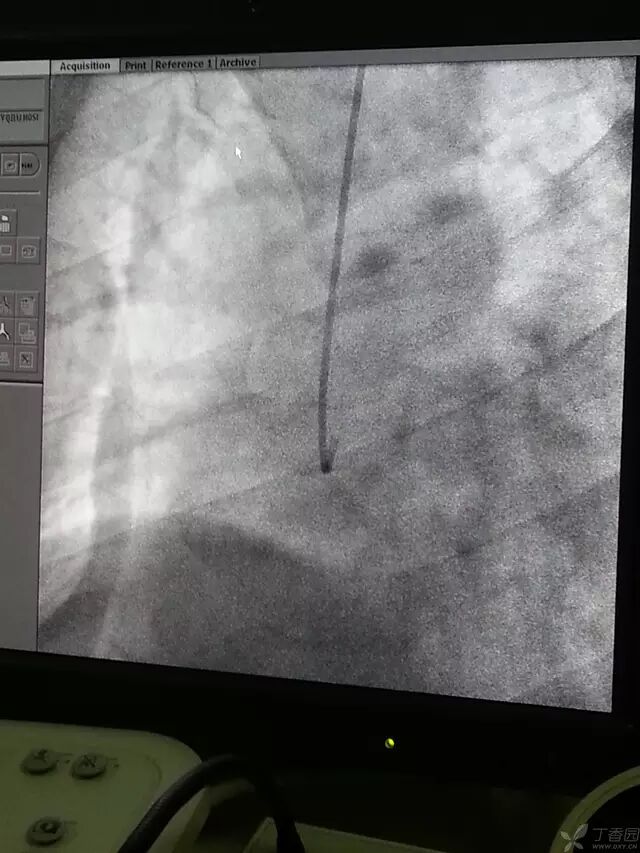

右冠造影的难度较之左冠更大。一般新手会很容易回撤过多。这是使导管上升至气管分叉影左右了。这是不要慌,旋转导管,一般为顺时针,使导管 L 型头面向屏幕(使 L 成 I )送入导管至窦底,一般在窦底后会自动回呈 L 型,此时顺时针旋转导管,使之旋转为 I 状时,如图。

造影导丝是什么原来心脏造影这样做:冠脉造影全程图解_https://www.jmylbn.com_新闻资讯_第15张